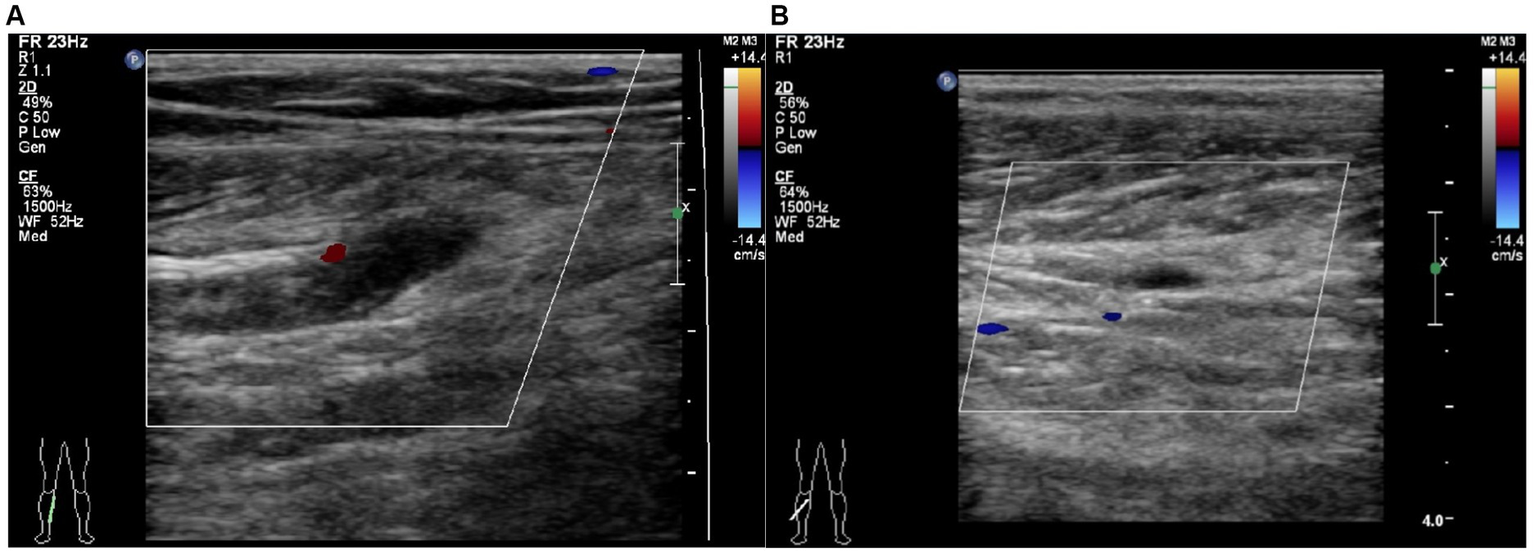

All patients routinely underwent Color Doppler ultrasound for thrombosis screening on admission. The diagnostic criteria for fresh thrombosis are solid echogenicity in the vessel and absence of blood flow signal or a constant intraluminal filling defect (Figure 1) (12). The Color Doppler ultrasound is conducted by an experienced sonographer in the ultrasound room. The results of all ultrasound tests were scrutinized by a senior sonographer, while any differing opinions were resolved through a re-examination of the ultrasound. All patients were reviewed for ultrasound every 3 days after admission. Venography was performed if the vessels were poorly visualized by ultrasound. If a patient develops signs and symptoms of DVT during hospitalization, repeat venography or ultrasound is performed. Signs and symptoms to look out for include changes in skin temperature and color, pain, and tenderness in the calf or thigh, swelling, and a positive Homans’ or Neuhof’s sign. According to guideline recommendations all geriatric hip fracture patients at our institution received DVT prophylaxis (13). The thromboprophylaxis regimen was implemented for each patient after admission, which included the use of elastic compression stockings, intermittent pneumatic compression, and chemoprophylaxis. The chemoprophylaxis regimen consisted of administering low molecular heparin (4,000 AxaIU/0.4 mL) or fondaparinux (2.5 mg) subcutaneously once daily. Patients diagnosed with DVT received anticoagulation and thrombolytic therapy.

Figure 1

Typical image for the diagnosis of calf muscular vein thrombosis by Color Doppler ultrasound. (A) Right partial calf muscular vein with thickened vessel diameter and weak echogenic signal filling in the vessel cavity without obvious blood flow signal. (B) Right partial calf muscular vein with weak echogenic signal filling in the vessel cavity and blood flow signal filling deficit.